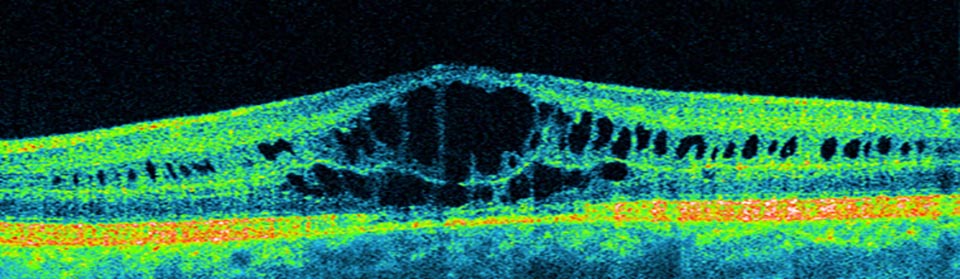

Almost 1 in 10 diabetics has sight threatening retinopathy.

Diabetes is the leading cause of blindness in the 25 to 75 age group.